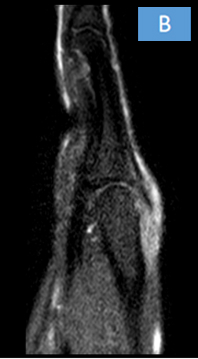

• There is ulnarward subluxation of the extensor digitorum tendon of the middle finger at the level of metacarpophalangeal joint.

• Mild edema seen in the surrounding soft tissue.

• Defect/tear in the sagittal band of the extensor hood of  the right middle finger.

• Mild intrasubstance STIR hyperintensity within the extensor digitorum tendon, suggesting tendinosis.

Tendinosis and ulnarward subluxation of extensor digitorum tendon of right middle finger at the level of metacarpophalangeal joint with defect/tear in the sagittal band of the extensor hood.